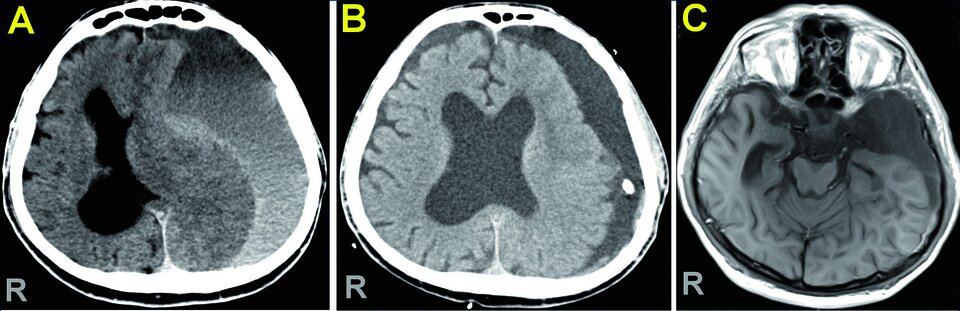

Mit rechtsseitiger Hemiparese, Aphasie und Vigilanzminderung wurde ein 43-Jähriger ins Krankenhaus eingeliefert. Die Verdachtsdiagnose zerebrale Isch­ämie bestätigte sich nicht. Stattdessen zeigte die CT ein ausgedehntes chronisches Subduralhämatom. Spuren einer Kopfverletzung waren nicht zu erkennen, die Gerinnungsdiagnostik einschließlich Thrombozytenfunktion blieb unauffällig. Auch bei diesem Patienten erfolgte die Entfernung des Hämatoms über eine Bohrlochtrepanation, was die linke Hirnhälfte deutlich entlastete. An ein relevantes Schädel-Hirn-Trauma konnte sich der Patient nicht erinnern. Die Ärzte hielten daher eine in der MRT sichtbare große Arachnoidalzyste am rechten Temporalpol für die wahrscheinlichste Ursache des Subduralhämatoms (s. Abb. 2).

Abb.2: Subduralhämatom mit massiver Verdrängung des Gehirns nach rechts in der MRT (A). Die Trepanation führte zu einer deutlichen Entlastung der linken Gehirnhälfte (B). Als Ursache zeigte sich eine große Arachnoidalzyste im Bereich des rechten Temporalpols (C). Abb.2: Subduralhämatom mit massiver Verdrängung des Gehirns nach rechts in der MRT (A). Die Trepanation führte zu einer deutlichen Entlastung der linken Gehirnhälfte (B). Als Ursache zeigte sich eine große Arachnoidalzyste im Bereich des rechten Temporalpols (C). © Schulz C et al. Wehrmedizinische Monatsschrift 2022; 66: 214-223; DOI: 10.48701/opus4-21 © Beta Verlag & Marketinggesellschaft mbH, Bonn